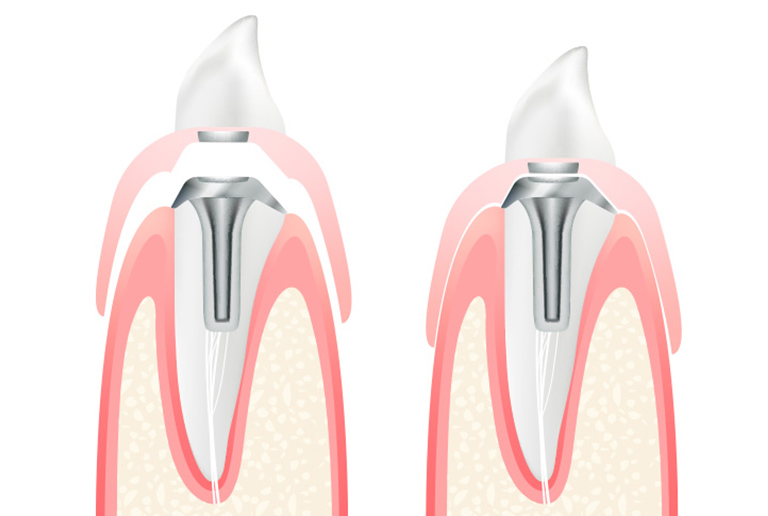

「部分入れ歯」は歯の一部分を失った場合に使用します。歯が持っている本来の機能を、残った歯と部分入れ歯で回復するように設計されています。

欠損部分の両隣の天然歯に、金属のバネ(留め具、クラスプ)をかけて固定します。

保険診療ではバネ部分が金属製になりますが、自費診療では金属を使用せずに、自然な見た目に仕上げることもできます。